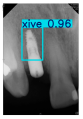

| Image Resolution = 825 × 1200 | ||||

| Test Image 1–4 | ![]() | ![]() | ![]() | ![]() |

| Accuracy | 94.13% | 95.29% | 92.88% | 91.80% |

| Recall | 96.71% | 94.03% | 93.88% | 92.15% |

| Model reference time | 6.57 ms | 7.08 ms | 7.12 ms | 6.43 ms |

| Dentists’ average diagnostic time | 2.78 s | 4.55 s | 7.78 s | 7.23 s |